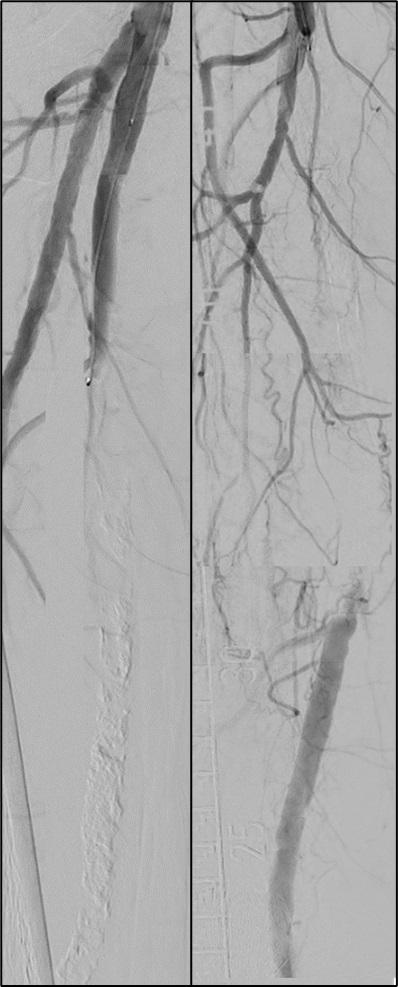

Pilot testing has shown that a new framework—dubbed Endo-STAR—can be used to describe and standardise endovascular interventions for peripheral arterial disease (PAD) within a randomised controlled trial (RCT) protocol and monitor adherence to the protocol over the course of a trial. Ewa M Zywicka (University of Bristol Medical School, Bristol, UK) shared this conclusion during the Prize Session at the recent European Society for Vascular Surgery (ESVS) annual meeting (24–27 September, Kraków, Poland).

ZYWICKA BEGAN BY NOTING THAT

rigorous evaluation of novel lower-limb endovascular interventions is “critically important” to ensure adoption of effective technologies and rejection of those that are ineffective or harmful.

The presenter continued that poor reporting of RCTs limits the evaluation of technologies for lower-limb endovascular interventions, highlighting a recent study in which more than half of RCTs did not adequately describe interventions, and almost 80% did not report any form of standardisation.

The aim of Zywicka and colleagues’ present study, therefore, was to develop a specific framework for describing and standardising endovascular lower-limb interventions within clinical trials.

Zywicka explained to the ESVS audience that the Endo-STAR framework was developed using qualitative research methodology and the Enhancing the Quality and Transparency of Health Research (EQUATOR) methodological framework. The presenter added that trial reports and associated protocols identified in a recent systematic review of endovascular infrainguinal lower-limb RCTs for PAD provided the data for developing the preliminary framework.

Going into more detail about the research methods used, Zywicka detailed that a framework approach to thematic analysis of qualitative data was employed to code and categorise text into steps and components of endovascular infrainguinal interventions.

Subsequently, focus groups were conducted

with key international stakeholders such as clinical practitioners—namely vascular surgeons, interventional radiologists, angiologists and cardiologists—trialists, industry representatives and journal editors to refine the framework and consider clarity and feasibility issues. Zywicka noted that the framework was updated based on this feedback, and

a consensus between stakeholders was reached via a modified Delphi-style questionnaire.

Finally, Zywicka shared, the framework was refined through cognitive interviews with trialists to test the real-world feasibility of using the Endo-STAR framework in contemporary endovascular RCTs. An online version of the Endo-STAR framework

Twenty-four key stakeholders participated in three focus groups, contributing to the refinement of the framework

was developed to facilitate implementation and dissemination.

At ESVS, Zywicka informed attendees that the preliminary framework was developed after including data from 112 RCTs evaluating endovascular infrainguinal interventions for PAD.

Zywicka relayed that 24 key stakeholders participated in three focus groups, contributing to the refinement of the framework, and all 24 participants took part in the consensus questionnaire. After the first round of the questionnaire, the presenter continued, an agreement above 85% was reached for each framework section. Ten trialists involved in contemporary endovascular trials took part in pilottesting the framework.

Ultimately, Zywicka reported, the Endo-STAR framework was structured into six main sections: 1) expertise of the professional delivering the intervention, 2) setting/location of the intervention, 3) anaesthesia provided for the intervention, 4) imaging used at the time of the intervention, 5) intervention components: access, crossing the lesion, treating the lesion (including specific steps and details related to all currently available endovascular devices) and closure of the artery, and 6) pharmacological interventions.

In discussion time following Zywicka’s talk, jury member Jon Boyle (Cambridge University Hospitals NHS Foundation Trust, Cambridge, UK) asked how the framework might help in terms of monitoring long-term outcomes of endovascular interventions, to which the presenter responded: “What we are aiming to achieve with this framework is to know what has been done in a trial […] we expect that actually being able to know and clearly describe what was done in a trial can be used to easily compare trials and even potentially compare results in the long term as well.”